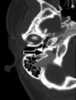

A congenital lip pit or lip sinus is a congenital disorder characterized by the presence of pits and possibly associated fistulas in the lips. They are often hereditary, and may occur alone or in association with cleft lip and palate, termed Van der Woude syndrome. [Source: Wikipedia ]